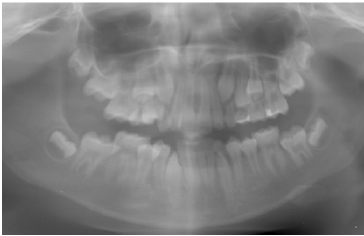

At the 2021 follow-up, when the patient was 9 years old and in the mixed dentition stage, oral examination indicated moderate oral hygiene. Clinically, the eruption sequence of permanent teeth appeared age-appropriate. A panoramic radiograph confirmed these findings, showing localized vertical bone loss adjacent to the mandibular central incisors, while the remaining dentition displayed normal eruption patterns without other pathological changes (Fig. 2). Professional cleaning and scaling were performed. Preventive measures were reinforced, including topical fluoride application and placement of sealants on the permanent first molars, aiming to enhance caries resistance during the mixed dentition phase.

Panoramic radiograph at age 9 (2021), showing localized vertical alveolar bone loss adjacent to the mandibular central incisors, with the remaining dentition demonstrating a normal eruption sequence.